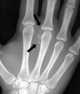

Periarticular calcification